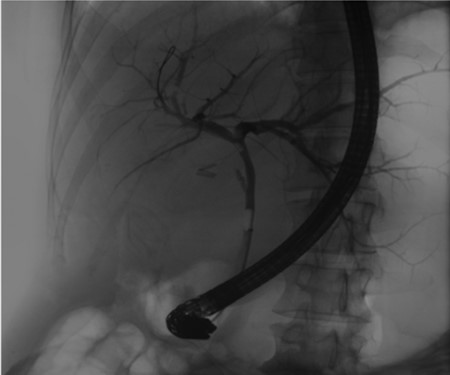

Post-operative ERCP displaying left sided intrahepatic duct biliary dilatation.

A 35-year-old female with a medical history significant for acute biliary pancreatitis status post laparoscopic cholecystectomy, presented to the surgery clinic as a new consult for a large cystic liver mass with increasing abdominal pain for 2 weeks. Patient reported suffering from severe pain in right chest, shoulder and diffuse abdominally that worsened with standing. Patient complained of inability to inspire due to pain and a 10-pound weight gain over 2 months. She confirmed decreased appetite especially with solids, nausea and emesis, alternating constipation and diarrhea, bruising, and pruritus at night. Computed tomography (CT) scan demonstrated a peripherally septated 10 x 7 cm cystic mass in the liver with intrahepatic biliary dilation (Fig. 1). The patient was referred for endoscopic retrograde cholangiopancreatography (ERCP) to establish preoperative biliary anatomy and was found to have moderate compression of the common hepatic duct managed with a right hepatic biliary endoprosthesis (Fig. 2); no obvious communication of the biliary tree with the cystic lesion was seen. Patient symptoms persisted despite optimizing with a protein-rich liquid diet; thus, the decision was made to proceed with the surgical plan for an open partial central hepatectomy. The patient was taken to the operative theater. After induction of general anesthetic, an upper midline incision was made. Inspection of the abdomen and liver showed no metastatic lesions grossly or with ultrasonographic imaging. The cyst was visible upon entry into the abdomen with no solid component to the mass in proximity to the cystic neoplasm. The second portion of the duodenum was adherent to the cyst with inflammatory adhesions and was quite boggy. A partial central hepatectomy was performed; a 3 mm biliary duct was found communicating to the cyst only with no drainage to the minimal liver parenchyma that was removed (Fig. 3). The cyst was resected en-bloc and was sent for permanent section (Fig. 4), which diagnosed the tumor as a low-grade mucinous cystic neoplasm measuring 8.5 × 7.2 × 6.4 cm. Microscopy revealed a smooth-walled, multiloculated cyst filled with a yellow-golden, semi-transparent and mucinous fluid (Fig. 5a–c). The cyst was lined by a mucinous epithelium with ovarian-type stroma. No high-grade dysplasia or malignancy was identified. The postoperative course was uneventful, and the patient was discharged on postoperative day 6. At the 4-week postoperative visit, the patient was healing well with some incisional soreness; patient was seen for removal of her biliary endoprosthesis, and ERCP found left sided intrahepatic duct biliary dilatation including a small biliary fistula from the left system (Fig. 6) with the appearance of torque on the extrahepatic biliary tree. A biliary endoprosthesis was left in place, and the patient returned for repeat ERCP 4 weeks later with resolution of all findings (Fig. 7). At present, patient remains alive with no signs of recurrence.